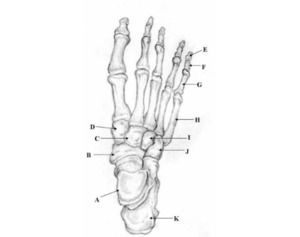

Two unlabeled illustrated images, figures 1 and 2, of the foot and one unlabeled x-ray image, figure 3, were selected. Each image was inputted into ChatGPT Version 4o and the model was prompted to identify the bones depicted in each image using the following prompt.

Prompt 2: ‘Identify the structures labeled in this image’

Prompt 2: Identify the structures labeled in this image

Out of 7 labels, 4 were identified correctly, resulting in an accuracy of 57%.